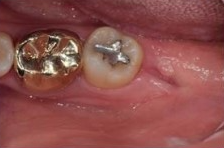

아래 케이스를 보면 위아래 사랑니가

정상 맹출되었으나 충치가 진행되어

주변치까지 영향을 주기 전에

발치를 진행하였습니다.

사랑니 발치 후 회복과정 한 눈에 보기 / 강남역 사랑니 강남레옹치과